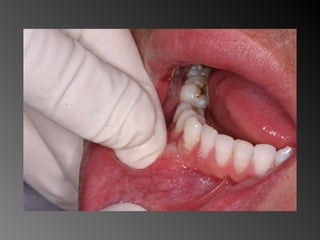

Granuloma (Lesão) Periférico de Células Gigantes A excisão cirúrgica deve ser antecedida de exame radiográfico, pois lesão não completamente removida e/ou com infiltração óssea, pode recorrer

Granuloma (Lesão) Periféricode Células Gigantes A excisão cirúrgica deve ser antecedida de exame radiográfico, pois lesão não completamente removida e/ou com infiltração óssea, pode recorrer

26 - Pacientedo sexo feminino, 30 anos de idade, se apresentou com aumento de volume no corpo da mandíbula, região dos dentes 45, 46 e 47, assintomático e com evolução de aproximadamente 1 ano. Pelo exame clínico constatamos expansão óssea e deslocamento dos dentes 45 e 46 de suas posições normais. Através de radiografia panorâmica observamos uma imagem radiográfica multilocular onde as trabéculas ósseas se encontravam perpendicularmente umas às outras e em outras regiões com aspecto de bolha de sabão. Com base no quadro clínico, o diagnóstico é: a) Ceratocisto e mixoma odontogênico. b) Odontoma composto e ameloblastoma. c) Mixoma odontogênico e ameloblastoma. d) Mixoma odontogênico e odontoma composto. e) Ameloblastoma e ceratocisto.